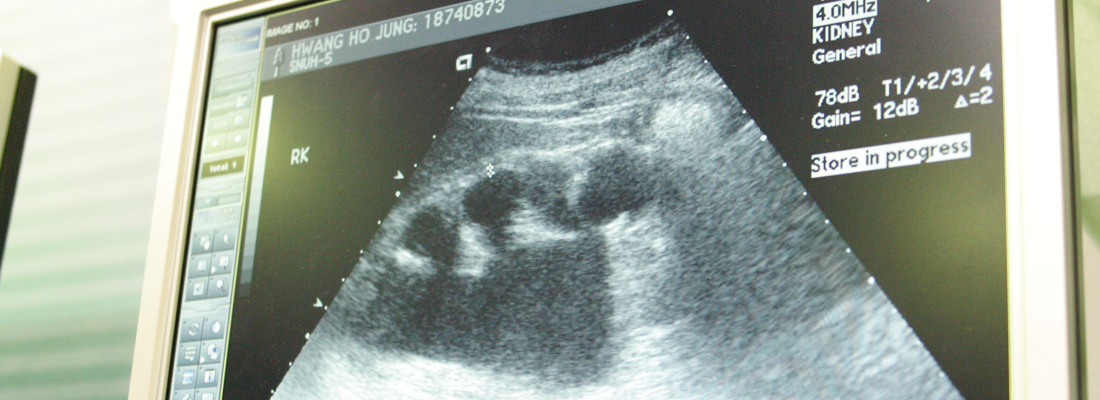

태아 초음파 검사 태아 초음파 검사는 임신 19주에서 24주 사이에 시행하며 전 임신의 3~5%에서 발생하는 선천성 기형을 산전에 발견하는데 매우 유용합니다.

초음파는 인체에 무해하여 비교적 장시간 검사를 하여도 산모나 태아에 특별한 해는 없습니다. 다만 검사 시간이 길어서 산모가 다소 피로함을 느낄 수 있습니다.